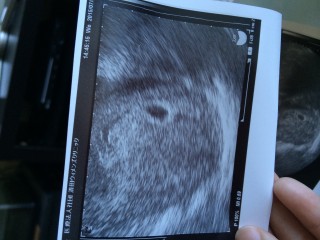

40歳で初の妊娠です。卵管通水検査をした週に妊娠しました。 先週は、ちいさな胎嚢だけみえましたが、今回は14.1㎜の胎嚢と卵黄嚢が見えました!来週には胎芽が見えるかなぁ、楽しみです!

4w5dの時に初診でしたが、全く何も見えませんでした。そして、今日無事に胎嚢確認出来ました。まだ胎嚢のみで、胎芽は見えなかったけど、来週まで待ち遠しいです。

卵黄嚢、胎芽、心拍の確認が出来ました!心拍見えるかな?と先生に言われ見てみるとピコピコ動いていて安心しました。胎芽の大きさは3.3mmでした。

1週間前に受診した時には、まだ何も見えなくて不安な日々を過ごしていました。2回目の受診で子宮内にしっかりと胎嚢確認できました。とっても嬉しかったです。まだ胎嚢のみで胎芽は見えなかったけどこれからすくすく大きくなってね!

4週で検査薬くっきりだったので すぐ病院に行くと『子宮は妊娠する時の形だねー』と 言われたけどその時は胎嚢確認できず(T_T) 5週でやっと1㎜の胎嚢が確認できました♫ 2週間後の検診が楽しみです!